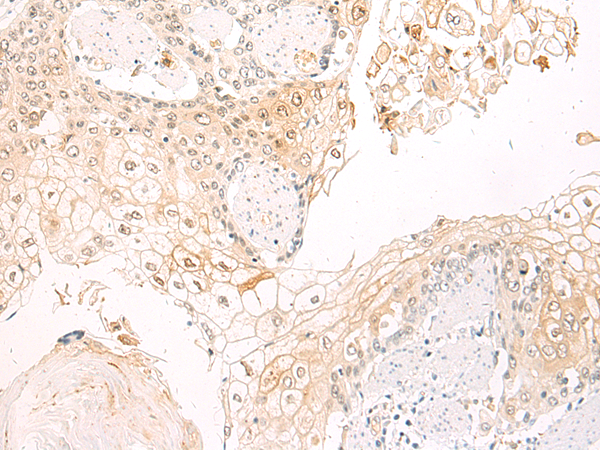

IHC positive control: |

Human esophagus cancer |